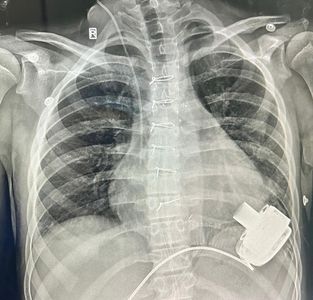

Gurugram, India: This 14-year-old boy is now the first child to be discharged in Northern India after receiving a Mechanical Heart- A Left Ventricular Assist Device. He is now also the youngest recipient of an LVAD device, in India. This pioneering surgery was performed at the department of Pediatric cardiac surgery, Artemis Hospitals, Gurugram.

After a complex and difficult surgery that involved connecting a Mechanical Heart Pump to the main pumping chamber of the heart and then connecting the other end (outflow) to the Aorta- the artery that takes blood to various organs of the body. The whole pump is so small that it sits inside the chest and connects to a computerised controller and battery through a small wire that comes out of the skin. As the device was started, it pumped blood from the left ventricle to the body and within a few days in the Pediatric Cardiac ICU, his organ functions started recovering.